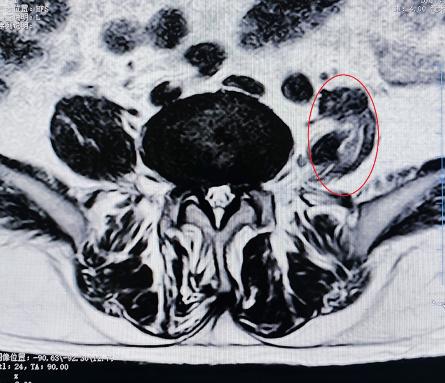

腰椎小关节增生紊乱:腰椎后方两侧成对的小关节,负责稳定脊柱并引导活动。它们如同门上的合页,一旦因劳损、退变导致软骨磨损、骨质增生,或发生微小错位,就会引发深层、定位模糊的腰痛。疼痛常在腰部扭转、后伸时加剧,有时晨起僵硬感明显。